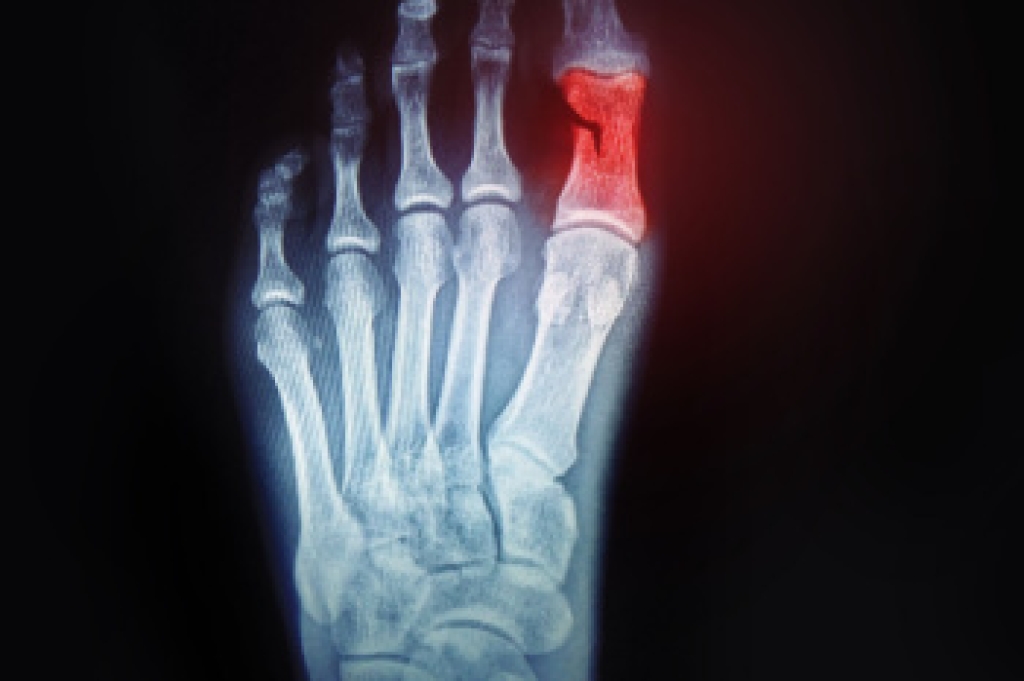

What Are the Symptoms?

- Mild to moderate bruising

- Limited mobility

- Swelling

- Discoloration of the skin (depending on severity)